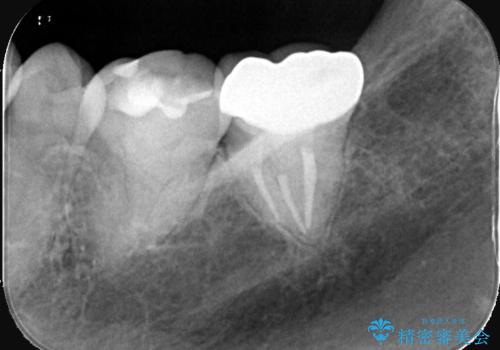

- 患者様は、他院で根管治療を受けたものの、違和感が続くため「しっかりとした治療を受けたい」とのご希望で来院されました。診査の結果、根管内の感染が完全に除去されておらず、根の先に炎症が残っている状態でした。そこで、精密根管治療を行い、感染源を徹底的に除去する計画を立てました。マイクロスコープを使用し、4回の治療で根の内部を清潔にし、最終的にしっかりと密封することで、長期的な安定を目指しました。

治療は、まず根管内の古い充填材を取り除き、感染部分を徹底的に洗浄・消毒することから始めました。ラバーダム防湿を使用し、治療中の細菌感染を防ぎながら、マイクロスコープを用いて根管の細部まで確認しながら処置を進めました。4回の治療で感染の除去と根管の封鎖を行い、最終的に土台を立てて被せ物の準備を整えました。患者様からは「違和感がなくなり、噛んでも痛くない」と喜びの声をいただきました。